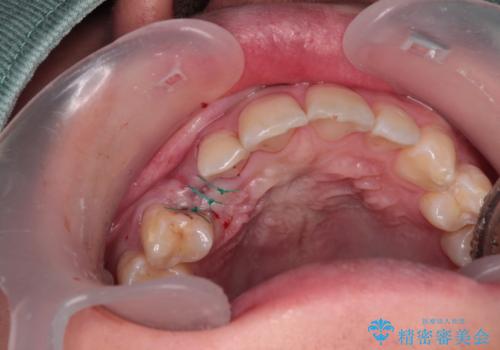

- 永久歯が生えてこず、欠損になっていることを気にして来院された患者様です。

CT撮影を行ったところ、埋もれている犬歯を牽引して萌出させることは不可能と判断し、インプラントによる補綴治療を行うこととしました。

現在では、埋入時に仮歯を装着する「即時荷重インプラント」での取り扱いとなりますが、治療当時は未導入であったため、従来の複数回の外科処置を行う術式で治療を行いました。